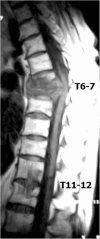

Recent findings: Recent studies have focused on risk factors for failed nonoperative management in order to improve patient selection. Also, spine instrumentation and different grafting options have been safely utilized in the setting of an active infection without increasing the incidence of reoccurrence. However, the optimal surgical technique has yet to be established and instead should be patient specific. Spine infections include a broad spectrum of disorders including discitis, vertebral osteomyelitis, and spinal epidural abscess. It is paramount to recognized spine infections early due to the potential catastrophic consequences of paralysis and sepsis. The management of spine infections continues to evolve as newer diagnostic tools and surgical techniques become available. Magnetic resonance imaging with contrast is the imaging study of choice and computed tomography-guided biopsies are crucial for guiding antibiotic selection. Antibiotics are the mainstay of treatment and surgery is indicated in patients with neurological deficits, sepsis, spinal instability, and those who have failed nonoperative treatment.